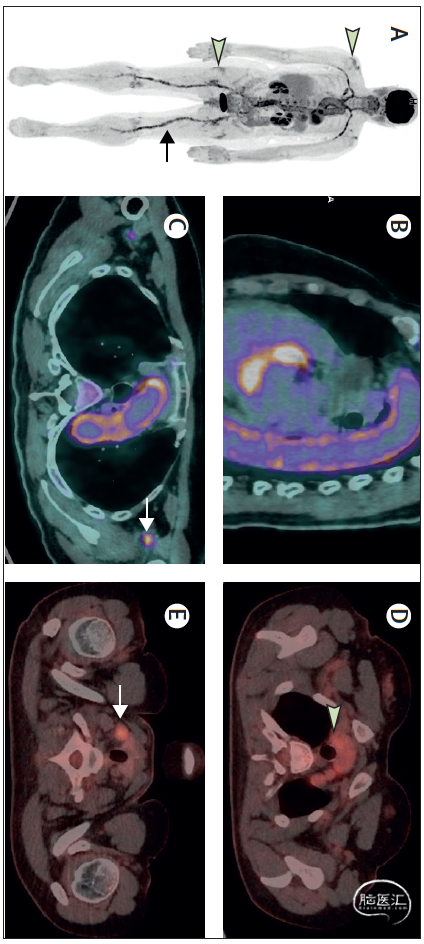

[¹⁸F]FDG-PET提供代谢信息(图4),主动脉炎定义为血管壁FDG摄取III级,其在区分血管炎与其他情况方面的敏感性为85%,特异性为83%。已发现[¹⁸F]FDG-PET无血管摄取对巨细胞动脉炎和大动脉炎的血管造影病变进展具有阴性预测价值。诊断时更广泛的血管高代谢(即较高的总血管评分)与病程中胸主动脉直径增加相关。由于血管摄取可能因血管重塑而非炎症而持续存在,除标记葡萄糖外,已测试了针对活化浸润巨噬细胞或组织驻留成纤维细胞的新标记物。

图4:[¹⁸F]FDG-PET扫描显示血管壁的FDG摄取。[¹⁸F]FDG-PET显示的动脉高代谢定义为III级FDG摄取(高于肝脏摄取),通常表现为环形高代谢。(A、B、C) 活动性巨细胞动脉炎患者的胸主动脉、锁骨下动脉、腋动脉(C图白箭头)、髂总动脉和股动脉(A图黑箭头)呈现明显高代谢。肩部棘突间隙及转子周围结节处亦可见显著高代谢(A图箭头),符合活动性风湿性多肌痛表现。(D、E) 活动性大动脉炎患者主动脉上干起始段可见中度高代谢(D图绿箭头),右侧颈动脉呈现不对称高代谢(E图白箭头)。FDG=氟代脱氧葡萄糖: